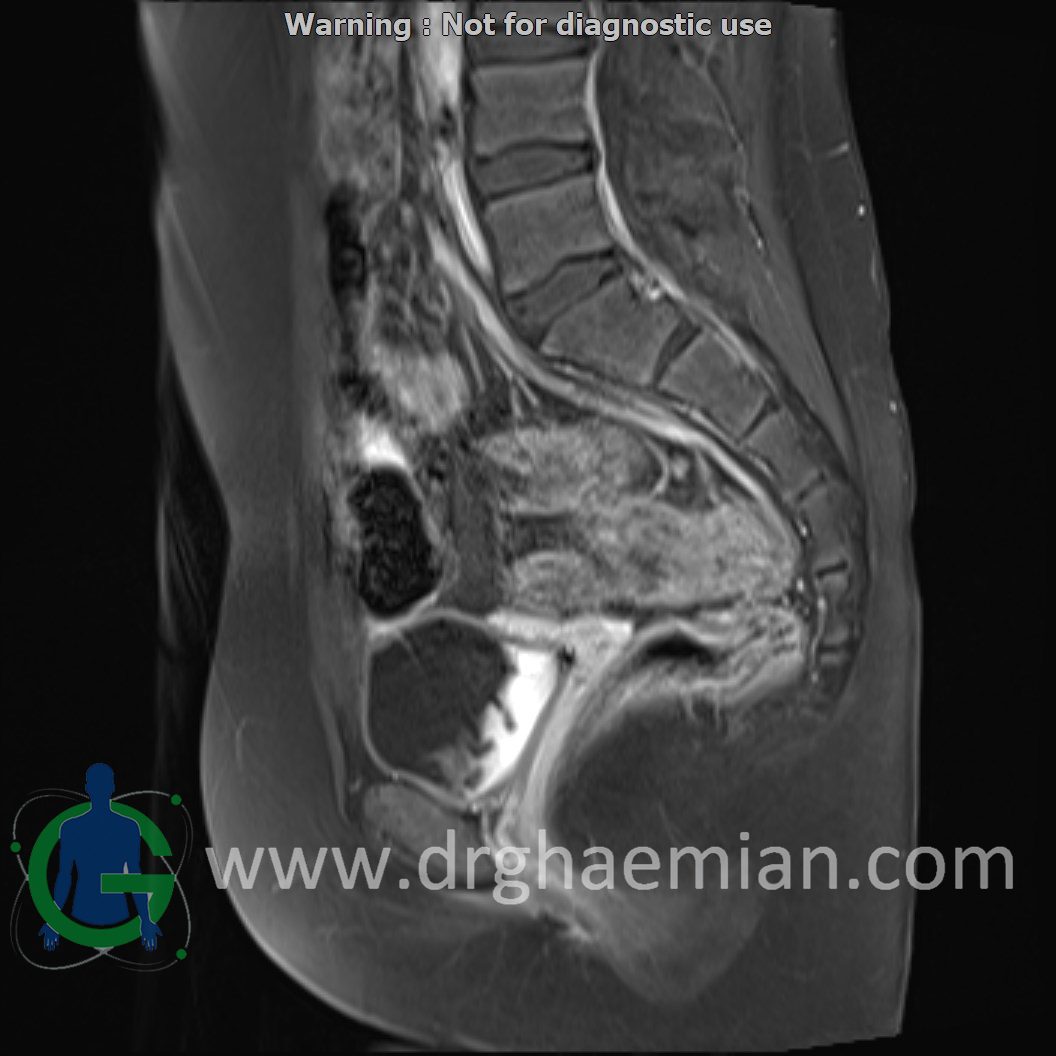

ام آر آی لگن یک روش تصویربرداری است که از طریق دستگاهی با آهنرباهای قوی و امواج رادیویی از ناحیه بین استخوان های ران تصاویری می سازد.در این کیس دیسژنزی غدد جنسی همراه با رحم و واژن هیپوپلاستیک نشان دهننده سندرم سویر ….

Complete gonadal dysgenesis with hypoplastic uterus & vagina suggestive of swyer syndrome is seen.

Clinical crrelation is recommended.